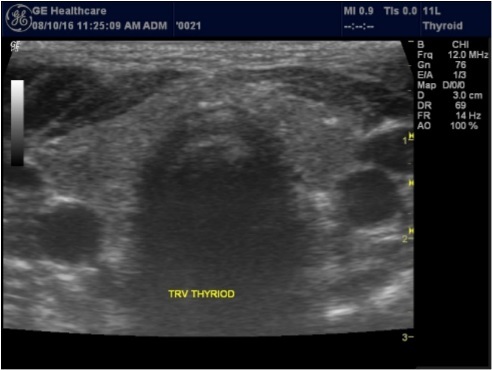

Color Doppler may be used to study the blood flow pattern of the thyroid gland, Figure 2. Thyroid blood flow may increase in some thyroid disorders like Graves' disease.

Figure 2.Blood flow pattern in normal thyroid gland

Blood flow pattern in normal thyroid gland